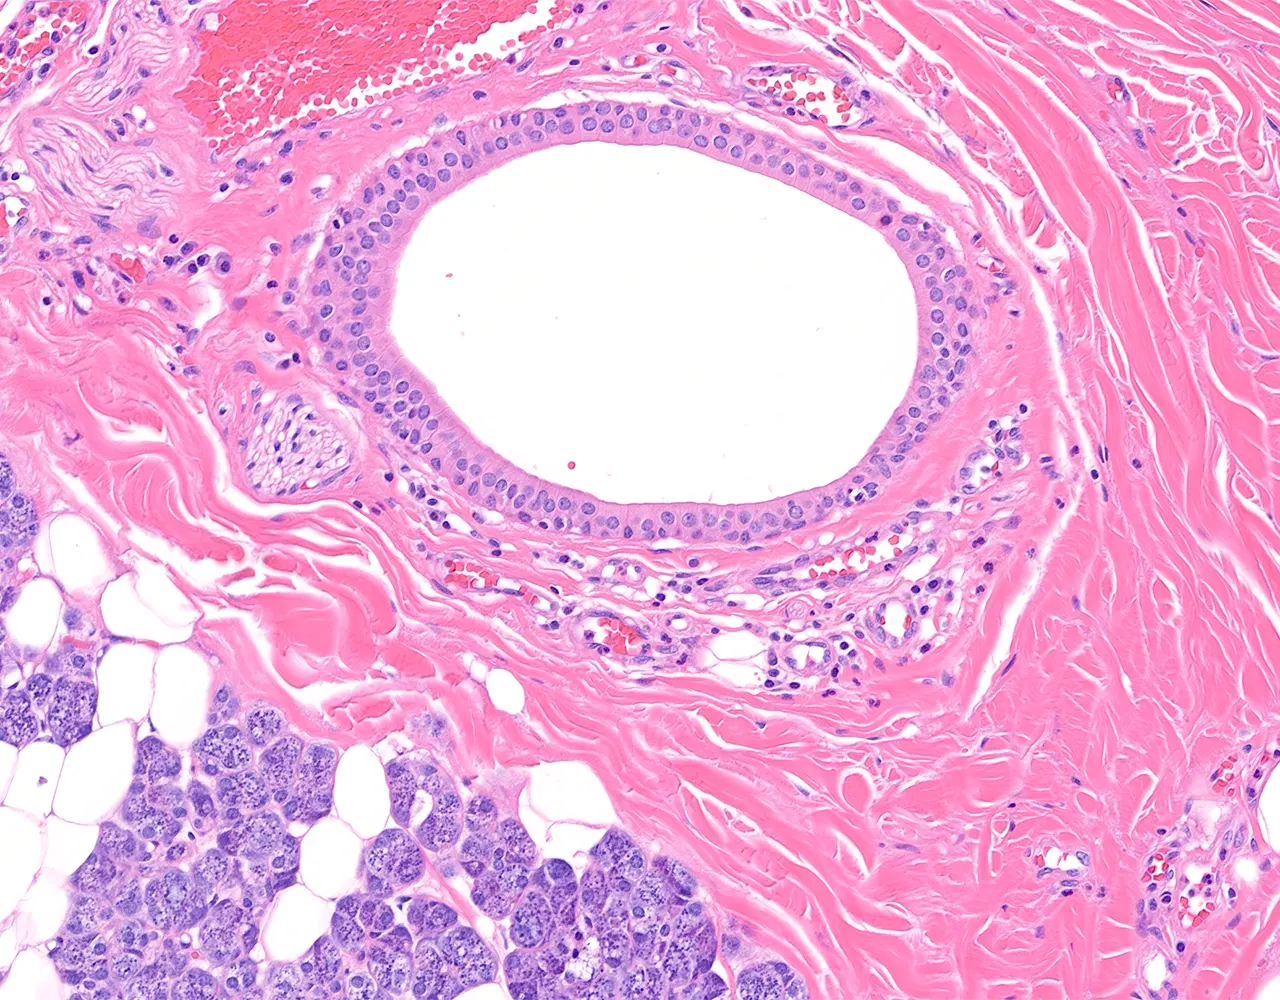

- Microscopically, the functional structure of a salivary gland consists of secretory acini and a duct system.